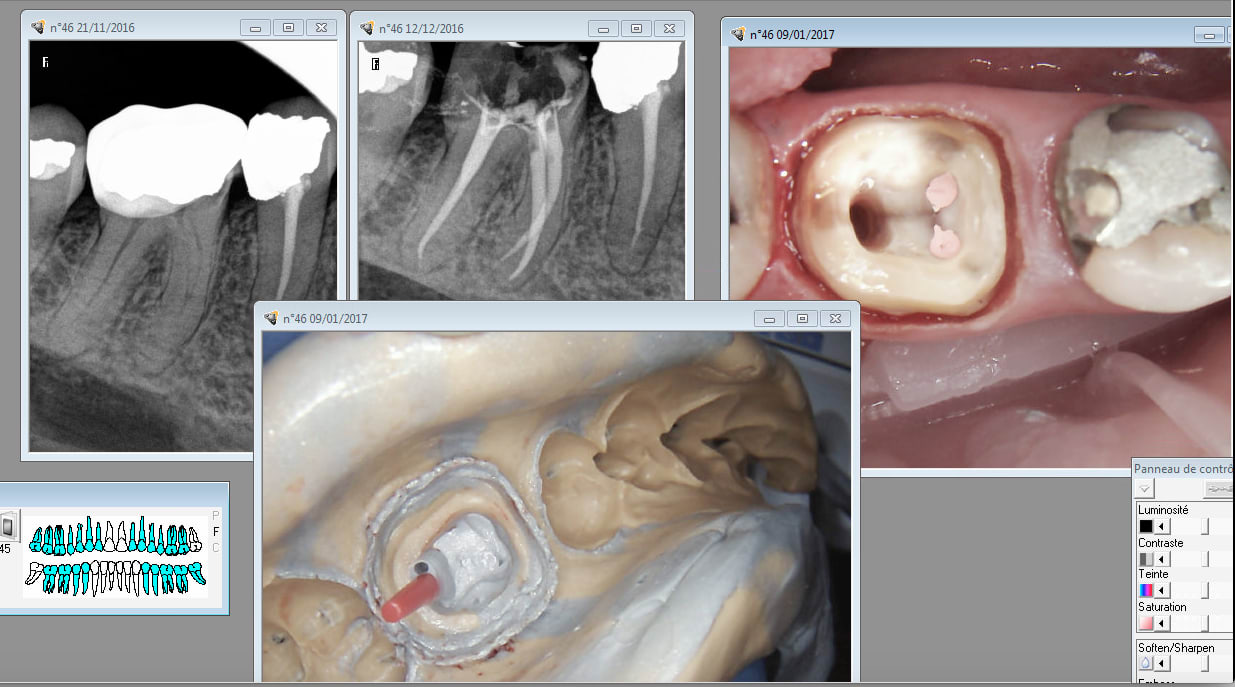

Edit : c'est ma bouche.

Vu la qualité de l'endo le confrère est tout excusé. -)

C'est quoi ce binz?! C'est des prépa supra gingivale?

Changes de dentistes... :-)))))